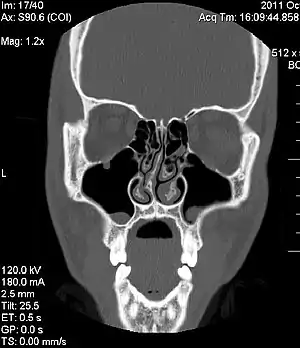

![]() Томограма конгенітально викривленої носової перегородки Томограма конгенітально викривленої носової перегородки | |